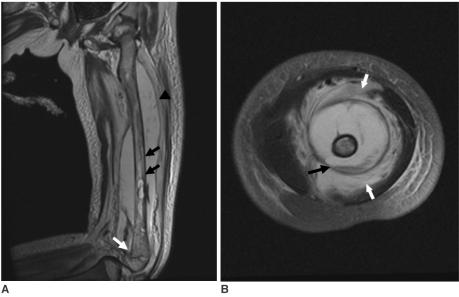

Scurvy is very rare disease in industrialized societies. Nevertheless, it still exists in higher risk groups including economically disadvantaged populations with poor nutrition, such as the elderly and chronic alcoholics. The incidence of scurvy in the pediatric population is very low. This study reports a case of scurvy in a 5-year-old girl with cerebral palsy and developmental delay based on MRI findings.

在工业化社会中,坏血病是一种非常罕见的疾病。然而,它在高风险人群中仍然存在,包括营养状况差的经济弱势群体,如老年人和慢性酗酒者。小儿群体中坏血病的发病率非常低。本研究基于磁共振成像(MRI)结果报告了一例患有脑性瘫痪和发育迟缓的5岁女孩患坏血病的病例。